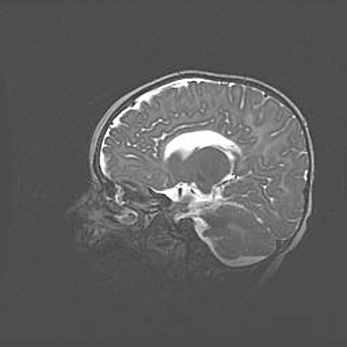

Аномалия Денди-Уокера. Признаки гипоплазии мозолистого тела.

Возраст: 5 месяцев 3 дня

Вес: 5550 г

Пол: мужской

Окружность головы: 39 см

Срок гестации: 40 недель

Аномалия Денди-Уокера – это порок развития головного мозга, для которого характерна триада симптомов: гипотрофия или аплазия червя мозжечка и/или полушарий мозжечка, расширение четвёртого желудочка с формированием ликворной кисты задней черепной ямки, гипертензионная гидроцефалия различной степени.

Гипоплазия мозолистого тела относится к дефектам внутриутробного этапа развития мозговой ткани, возникающим в процессе закладки структур головного мозга, что происходит на начальных этапах развития эмбриона.